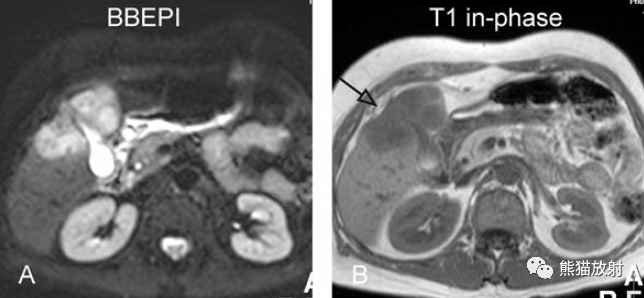

T2壓脂(T2 fatsat):膽囊窩內膽囊癌病變較肝臟為高信號,病變頂部向肝內擴展;

T1同相位(T1 in-phase):膽囊癌病變較肝臟為低信號;

增強動脈期(ART):不均質強化;

延遲期(DEL):部分廓清,部分持續強化。

膽囊癌。A~D圖:上方層面,表現如上所述,形成腫物侵及肝臟。E、F圖:下方層面示膽囊壁不規則增厚,明顯不均質強化。